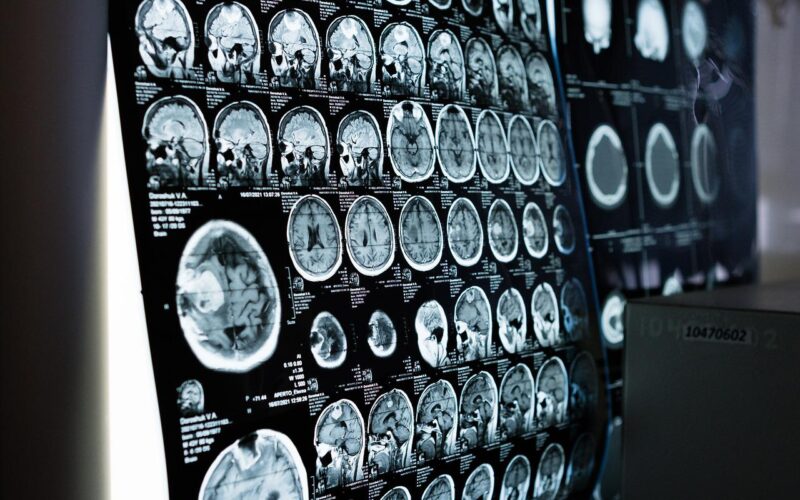

dugoročni učinci Zabrinjavajuće promjene uočene u mozgu pacijenata oboljelih od teškog covida-19 Na Sveučilištu Columbia, dr. Andrew Marks i suradnici proučavali su mozgove 10 pacijenata oboljelih od covida-19 i pronašli defekte u proteinima zvanim rianodinski receptori koji kontroliraju prolaz kalcija u stanice.